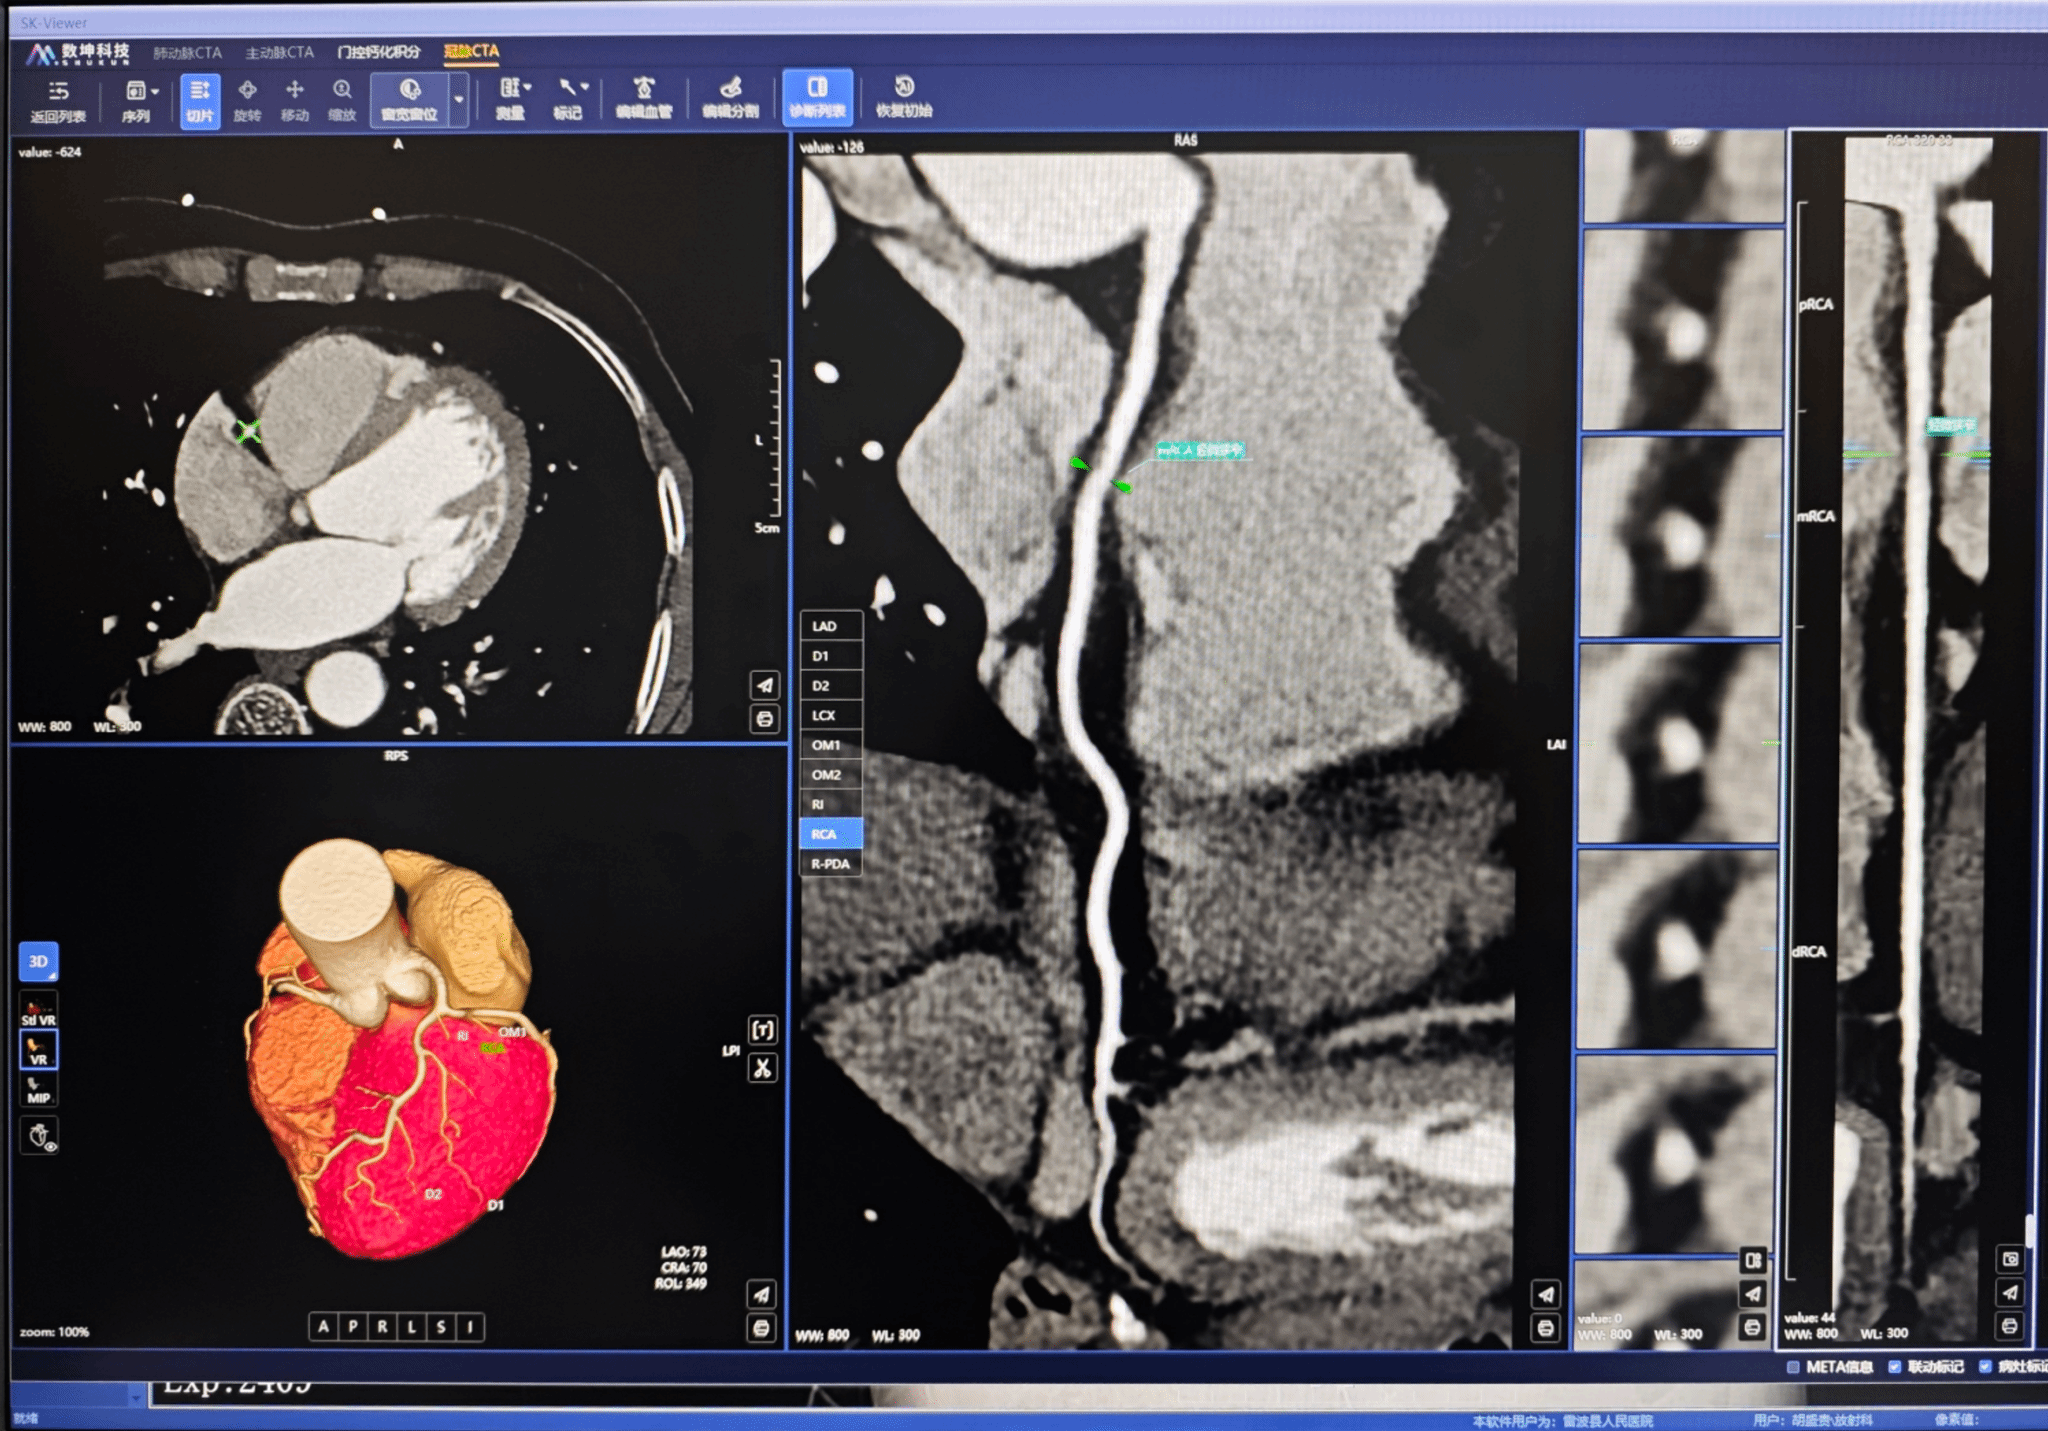

在夏林的精准把控下,团队从心率调控、呼吸屏气训练、造影剂注射方案优化、静脉通道精准选择,到图像重建后处理等全流程细化打磨,最终获取超高清冠状动脉影像资料,为临床精准诊疗提供了坚实依据。该院放射科海来不者老师看到重建图像后激动表示:“这是联影60排螺旋CT(uCT710)装机以来,我们获得的最优质冠脉CTA图像!”

夏林介绍,县级医院虽受设备条件限制,无双源CT等高端配置,但只要在各扫描环节精益求精、严控干扰因素,国产60排CT完全可产出高质量冠脉CTA图像,切实为基层患者健康保驾护航。